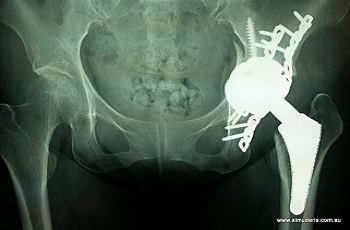

KNOW MOREHip replacement at Dr. Bagaria's Joint care by our Hip Replacement Doctor In Jaipur involves replacing the painful or arthritic hip joint with metal or ceramic and plastic components. It can be partial where only the ball of the hip is replaced or total where both the ball and socket of the joint is replaced.

KNOW MOREHip joints can be damaged due to arthritis, fracture, or other conditions making normal activities like walking, sitting, and standing difficult for the individual. Are you the one suffering from such a condition and want to consult the best THR doctor in Jaipur? The hip joint is considered as one of the largest ball-and-socket joints in the body made up of acetabulum, the part of the pelvis bone.